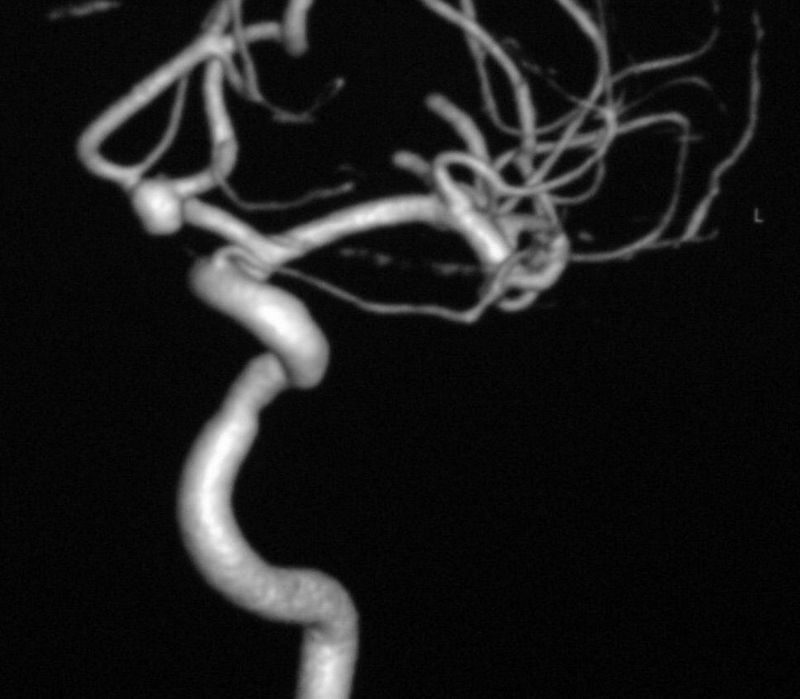

Imaging shows an anterior communicating artery aneurysm. Most neurosurgeons (if patient chosen craniotomy) would go with a pterional approach.